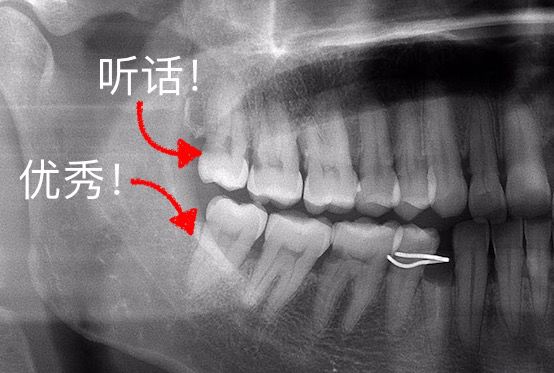

非阻生智齿则是健康生长的“三好学生”。

现实中阻生智齿的比例远超非阻生。如果你恰好是非阻生智齿,堪比中彩票的幸运!